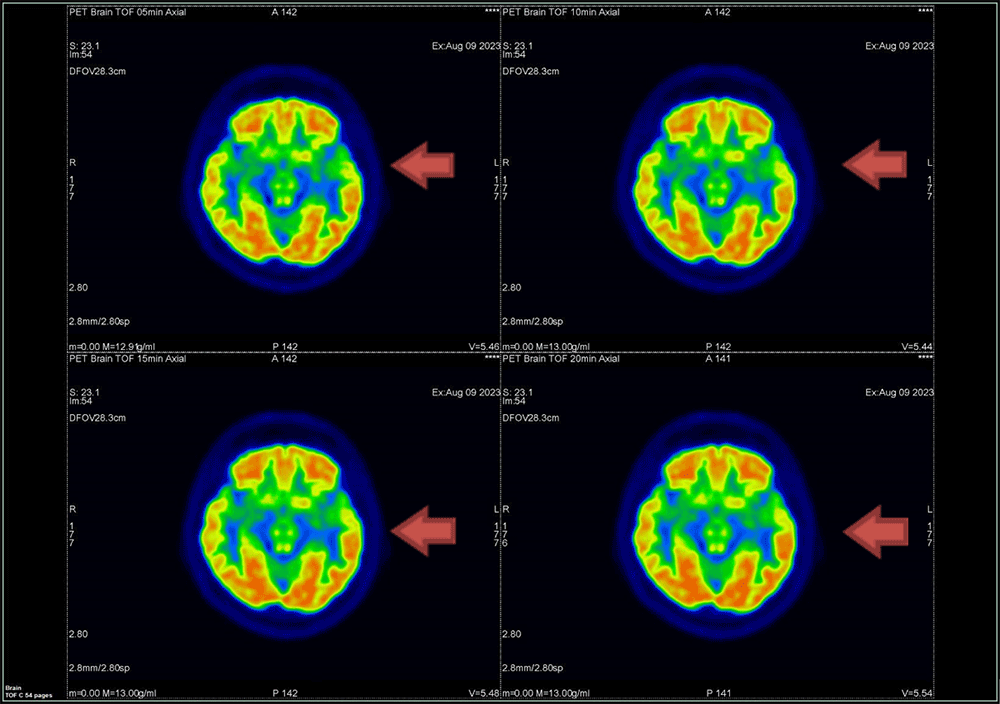

② Q.Clear法

β値150のQ.Clear画像をFig.6に示す。分解能の視覚評価では、マトリック数256以上では差を認めませんでした。

Fig.6 描出能の視覚評価 Q.Clear法(β150)